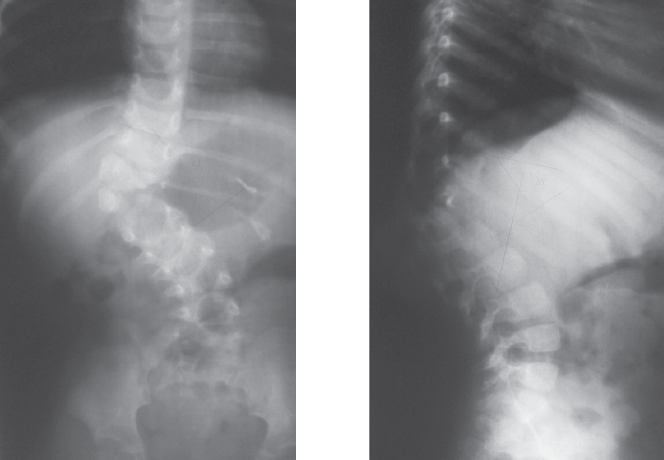

Clinical case of surgical treatment of advanced congenital kyphoscoliosis in 12 years old child is reported. Radiographs and CT at presentation failed to reveal the entire anomaly. By analysis of priorly made radiographs hemivertebra L1 was recognized. At genitourinary assessment L-shaped kidney was detected. A full-size 3D-printed model was used for surgical planning. Vertebral column resection as treatment option was discussed, but due to high neurologic complication rate this approach was refused. After preoperative 35 days halo-femoral traction anterior instrumented fusion was performed. Right ureter was stented for intraoperative urologic injury prevention. Scoliosis correction of 32% and kyphosis of 14% was achieved. 5 months later definitive posterior uninstrumented fusion was performed. Spinal deformities caused by vertebral malformations progress dramatically unless they are treated early. An advanced case is a clinical challenge because of technical difficulties and poor result. Vertebral column resection is a treatment option for severe kyphoscoliosis, but it’s indications should be strictly individualized. Preoperative halo-femoral traction is the most safe correction method in spinal deformity due to prolonged and gradual action. 3d-printed models are practical for surgical planning. The model may be used intraoperatively as a 3D-reference. In congenital scoliosis genitourinary system should be assessed meticulously, and urologist advice in relevant case is necessary.